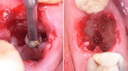

Degranulaatioporat

Puhdista luun pinta tehokkaasti pehmytkudoksesta.